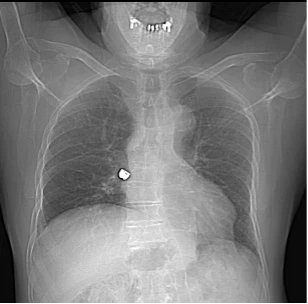

Un patient de 60 ans développe une dyspnée aiguë quelques heures après s’être rendu chez le dentiste. Il rapporte avoir subit plusieurs extractions dentaires et lors du moment du décompte des dents enlevées, il en manquait une. Le dentiste a conclu que le patient avait dû l’avaler. Par la suite, le patient présente une gêne thoracique motivant sa consultation aux urgences.

Le CT-scan thoracique, dont on voit ici le scout, met en évidence une structure hyperdense, de densité métallique, au sein de la bronche intermédiaire droite, pouvant correspondre à une couronne dentaire métallique, sans signe d’occlusion complète de la bronche. L’évolution est favorable après récupération de la dent logée dans la bronche intermédiaire droite par bronchoscopie.